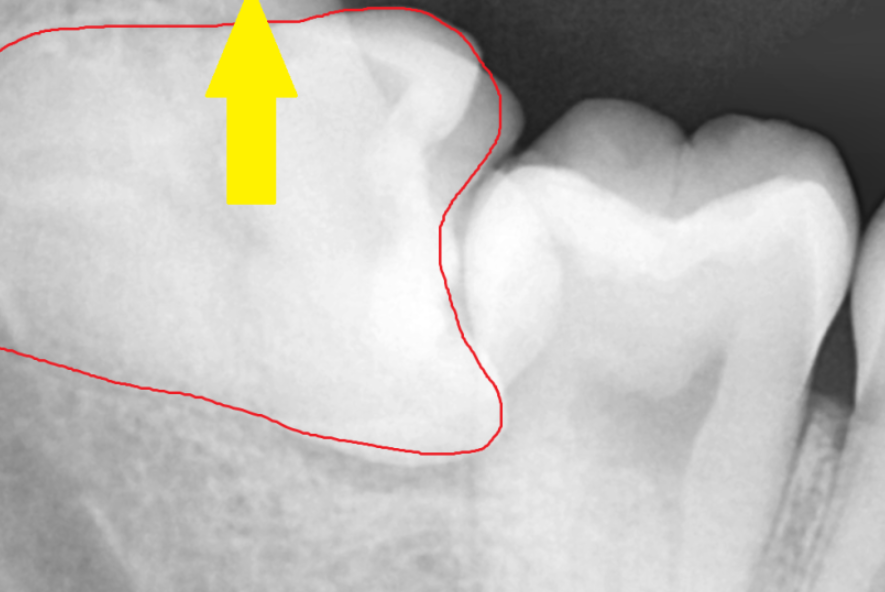

주변 치아에는 문제가 없나

x-ray를 통해 최최종 확인을 하고

치과에서

숨어있는 매복치 수술 진행했습니다.

주변 치아에 손상이 가지 않게

조각 조각 나누어 뽑아 주었습니다.

깔끔하게 잘린 단면 보이시죠?

이게 기술입니다!